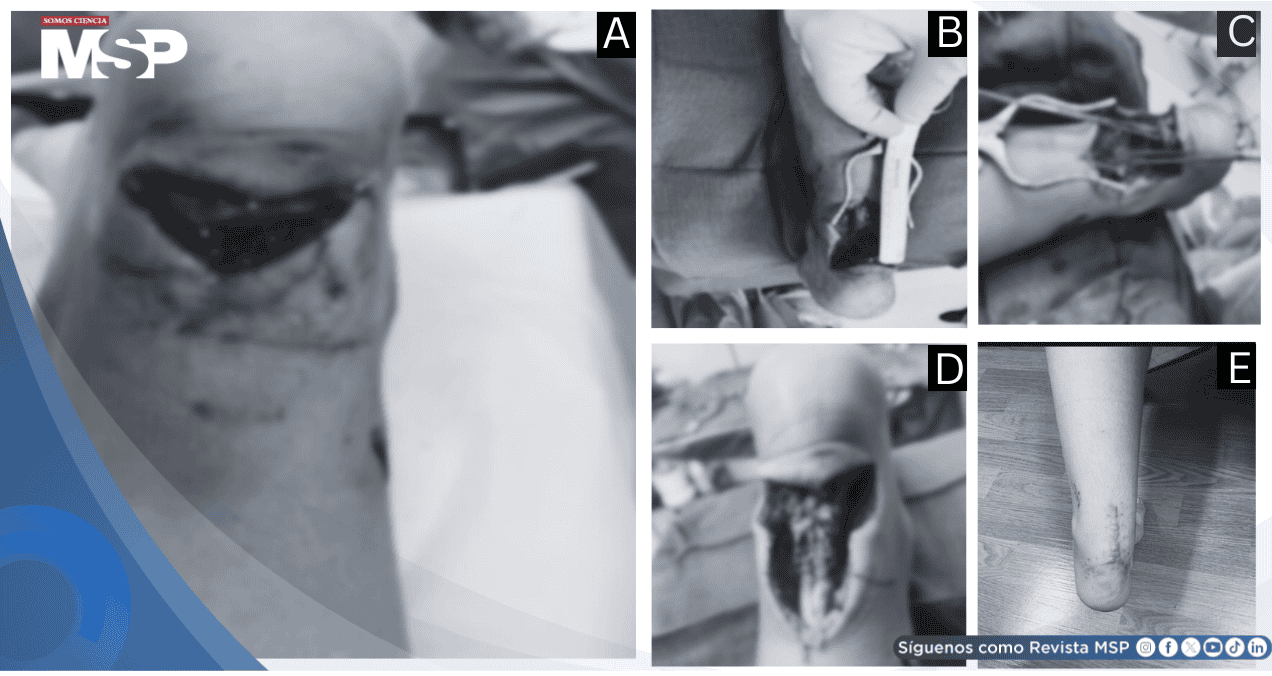

En la evaluación inicial, se evidenció una herida de 5 × 2 cm, con pérdida de continuidad del tendón de Aquiles visible macroscópicamente. La prueba de Thompson positiva confirmó la sospecha de rotura completa.

El paciente fue colocado en decúbito prono y se realizó una incisión longitudinal que incorporó la laceración original. Se identificó una ruptura distal del tendón de Aquiles, próxima a su inserción en el calcáneo. Se movilizó el extremo proximal y se efectuó un desbridamiento mínimo para permitir una aproximación anatómica sin tensión.

La reparación se realizó utilizando sutura FiberTape (Arthrex AR-9200-16s) con técnica de Krackow, aplicando puntos firmes a través de las porciones proximal y distal del tendón. Los extremos fueron ajustados para lograr una adecuada coaptación sin dejar espacio visible en la reparación.

Finalmente, se irrigó la zona, se realizó el cierre por planos y se colocó una férula corta de fibra de vidrio en flexión plantar de aproximadamente 30°. El paciente fue dado de alta al día siguiente con antibióticos orales durante una semana.

En la evaluación de control al año, se observó una cicatriz lineal completamente cerrada, sin signos de infección ni alteraciones funcionales.

El paciente presentaba un rango de movilidad de 10° de dorsiflexión y 45° de flexión plantar, con fuerza muscular 5/5 en los movimientos del tobillo y reincorporación total a las actividades cotidianas.